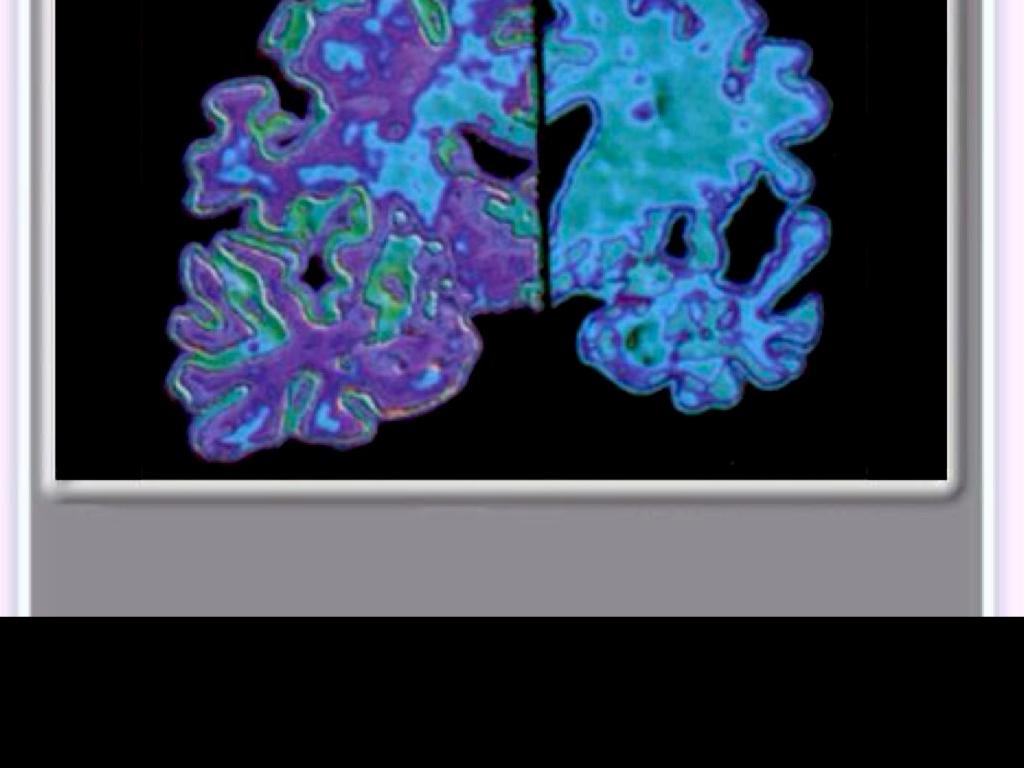

DEMENCIA TIPO ALZHEIMER

La enfermedad de Alzheimer es una enfermedad neurodegenerativa

inicio insidioso,

un declive progresivo de las funciones cognitivas con un pérdida fatal

PATOLOGÍA

lesiones neuropatológicas > depósitos proteicos

placas neuríticas compuestas por depósitos extracelulares de beta-amiloide (placas de b-amiloide)

Ovillos interneuronales >neurofibrillas ( enrrollados de la proteína tau citoesquelética).

hipocampo y en las áreas parietoremporales de la corteza cerebral